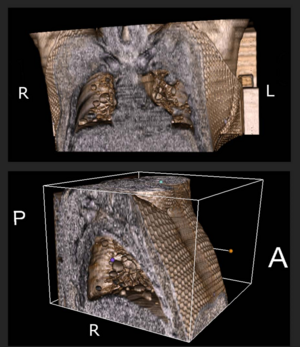

- 2.32 Three-dimensional Volumetric Rendition of Cannon Ball Pulmonary Metastases by the Use of 3D Slicer, an Open Source Free Software Package